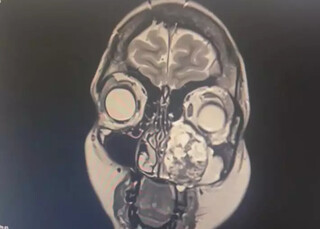

A descoberta veio ainda jovem, aos 19 anos, depois de insistência e de um sintoma que já não dava para ignorar: a visão começou a falhar. Foi só então que exames mais profundos revelaram o que nenhum médico suspeitava. Um tumor raro, um condrossarcoma que, em vez de aparecer em ossos, crescia na cartilagem do rosto, entre o seio nasal e a maxila.

Na época, aquilo foi um espanto para os médicos que ela consultou. O diagnóstico veio acompanhado de outra frase difícil de digerir: “nunca vi nada assim”. A 1ª cirurgia foi feita no Hospital Central do Exército, onde parte da estrutura interna do nariz precisou ser retirada. Sem quimioterapia ou radioterapia como opção, o tratamento se resumiu ao que ainda hoje é a única alternativa possível: cortar, retirar, acompanhar.

O problema tinha evoluído e estava invadindo o olho. Os médicos conseguiram tirar parte do assoalho e o canal lacrimal, mas a operação não foi tão fundo quanto deveria.

“Eles teriam que tirar o globo ocular e não era uma coisa que eles tinham me avisado antes da cirurgia, então eles não podiam fazer isso. Ela fez uma biópsia do que ficou e realmente constatou que também estava com algumas células doentes. Por mais que não tivesse retirado o tumor, ainda tinha ali um pouco das células”.